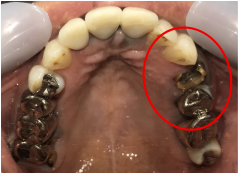

右下のブリッジがゆらゆら動く。

治療内容

ブリッジの支台になっている奥の歯が、被せ物の中で虫歯になり、支台の役割を果たさず、前方の歯のみで支えられていました。前方の歯をそのままにして、後方の部分を切り離すと、そのまま取れてきました。中は、虫歯で歯根しか残っていない状況でした。この歯は、根管治療後、単独でオールセラミック冠を被せ、歯のないところにインプラントを埋入しました。

所感

今回の治療法には、次の3つの方法があります。

(1)虫歯になっていた歯の根管治療をし、土台を入れ、また再びブリッジにする。しかし、虫歯になっていたほうの歯は、ブリッジの支台として使うには、心もとなく長持ちしない可能性が高く、今度問題が生じたときには抜歯になる。

(2)虫歯になっていた歯に、単独で被せ物をし、歯のないところに1本だけの部分入れ歯を入れる。取り外しの入れ歯なので、自分の歯のような感覚で噛むことはできない。この方法も歯のない部分の負担を欠損の両側の歯に負担してもらうため、長持ちしない可能性が高い。

(3)虫歯になっていた歯に、単独で被せ物をし、歯のないところにインプラントを埋入する。欠損している部分の負担を前後の歯に負担させないので、歯を守ることができる。また、自分の歯と同じ感覚で食事をすることができる。

患者さんは、3つ目の方法を選択されました。一番長持ちし、これ以上歯を失わないためには、最良の方法だと考えます。

Before

冠の中で大きな虫歯になり支台の役割を果たしていませんでした。

【インプラント埋入前】

冠はブリッジを切断しただけで取れてきました。軟化象牙質を取り除いたところ、歯根しか残っていない状況で保存できるかどうかのぎりぎりのところでした。

After